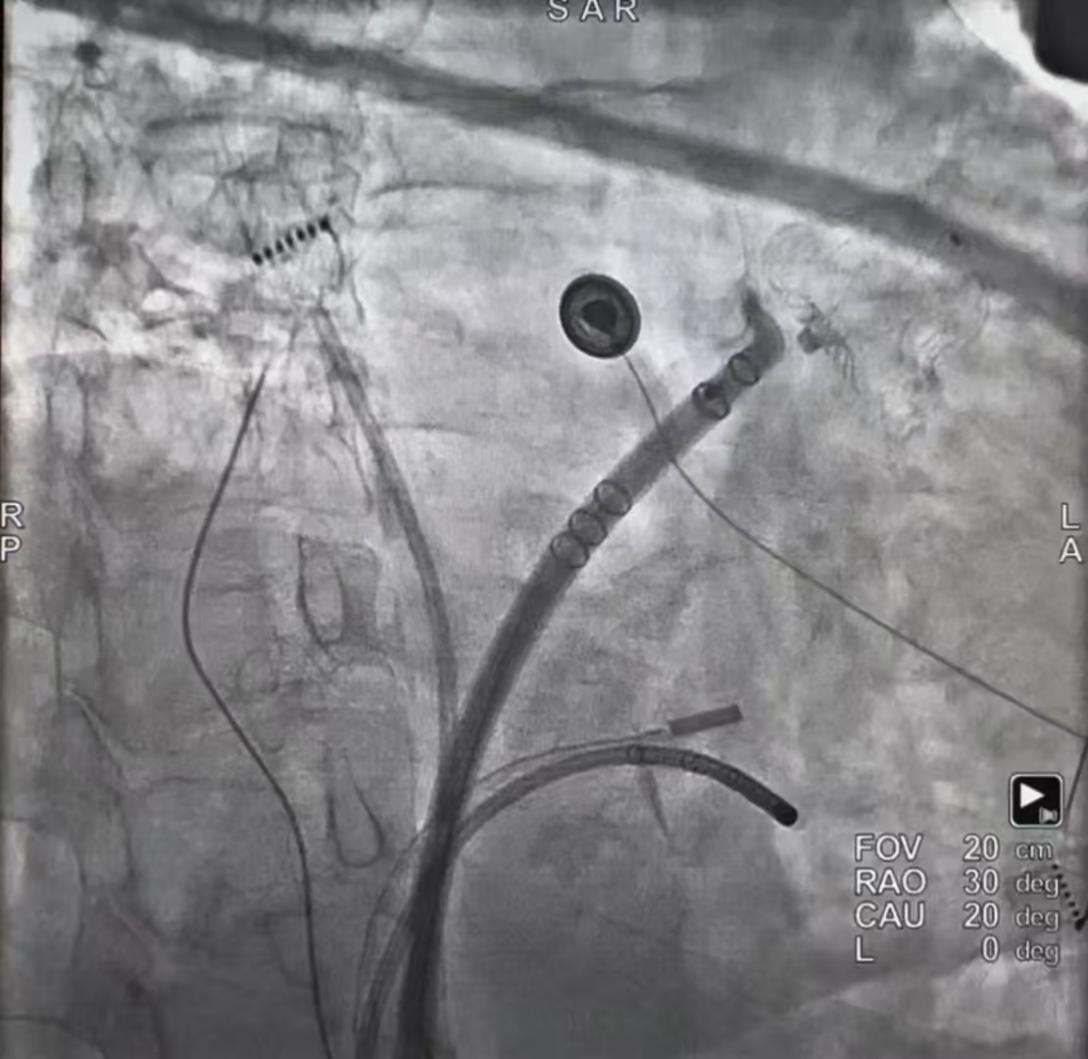

FARAPULSE脉冲导管以花瓣形态精准消融左上肺静脉

WATCHMAN FLX左心耳封堵器在左心耳内完美释放